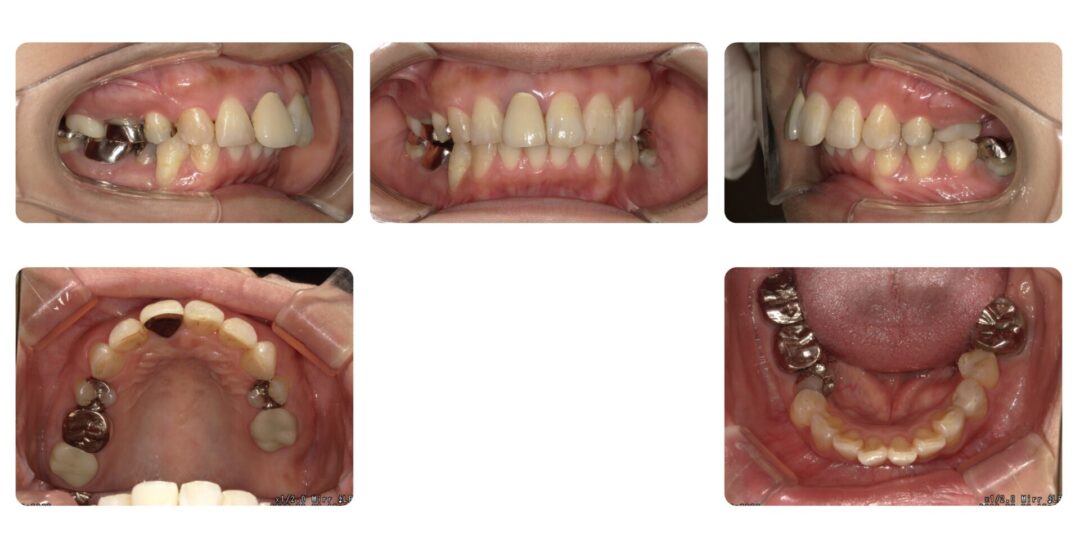

右下5番舌側転位を伴う骨格性上顎前突|初診時47歳

矯正治療前